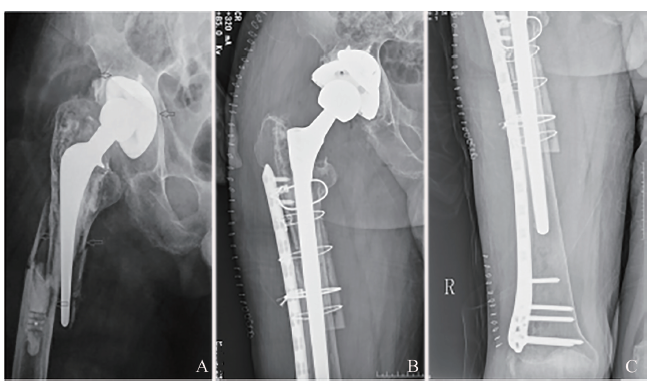

采用健侧卧位,取患侧髋关节后外侧切口,股骨头假体后脱位,取出股骨假体,初次THA采用骨水泥型股骨假体的患者要去除残留骨水泥,充分暴露骨折端。骨水泥组术中应用骨水泥型长柄股骨假体,均于修整髓腔后将调好的骨水泥灌注髓腔,安放股骨假体,并仔细观察有无骨水泥渗漏至骨折端,尽可能保证无骨水泥渗漏,骨水泥凝固后选择合适大小的股骨头复位髋关节。生物组为使用生物型长柄股骨假体置入髓腔,在骨折端上下均捆扎环扎钢丝以提高稳定性。2组中骨缺损严重患者(图1A)均行同种异体骨植骨及钢板固定(图1B、C)。检查股骨活动度,于假体周围留置引流管引流。

图1 采用生物型长柄股骨假体治疗PFF前后的X线片

A:可见股骨假体周围骨折,假体松动,去除残留骨水泥后有明显骨量缺损,属Vancouver B3型;B、C:术中使用生物型长柄股骨假体,结合钢板内固定及钢丝环扎,因骨缺损明显,同时使用异体骨板植骨+锁定加压钢板固定

生物组23例患者中有3例死于与手术无关的原因,其中1例为随访1年后死亡,随访资料已纳入研究,另2例随访不足1年死亡,部分随访资料纳入研究。另有5例患者于术后1年内失访,其中2例存在部分随访资料可纳入研究,3例出院后即失访,故生物组共收集到20例患者的随访资料,16例资料完整。骨水泥组的19例患者中有4例死于与手术无关的原因,其中1例为随访1年后死亡,随访资料可纳入研究,另3例随访不足1年死亡,部分随访资料纳入研究。另有4例患者于术后1年内失访,其中2例存在部分随访资料可纳入研究,2例出院后即失访,故骨水泥组共收集到17例患者的随访资料,12例为完整资料。2组患者的性别、年龄、分型、术前Harris评分具可比性(P均> 0.05),见表1,2组中共有23例术前合并高血压病、冠状动脉粥样硬化性心脏病、2型糖尿病、骨质疏松等疾病。采用生物型长柄股骨假体治疗PFF的典型图例见图1